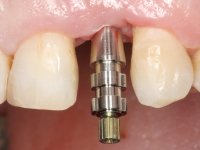

• Placement of an implant at the tooth site 2.2. Rehabilitation of the implant with a coronary and gingival component abutment. in which the screw access hole was "camouflaged" with a feldspathic veneer.

Treatment began with re-preparation of the cast post and core, with the purpose of placing the cervical finishing lines with an intra-sulcular location and simultaneously making a suitable temporary crown. With a very simple orthodontic treatment, the diastema was closed between the upper central incisors, and this position was stabilized with a wire placed on the palatal surface of the central, functioning as containment. Later, a slow orthodontic traction of tooth 2.2 was attempted, in order to reduce, although very slightly, the vertical bone loss in this area. At the end of the traction, tooth 2.2 was extracted and the area was provisionally rehabilitated with a composite resin crown bonded to the adjacent teeth. A dental implant was placed in the area of tooth 2.2 and the temporary crown was again bonded to resin, provisionally rehabilitating the patient during osseointegration. In tooth 1.3 a gingivectomy with an electric scalpel was performed, with the intention of raising the cervical level of 1.3 achieving greater harmony with tooth 2.3. Stabilized soft tissues were impressed using the open tray technique with putty and light addition silicones. Collection of the color of both the dental component and soft tissues was done by the ceramist in the office. In the laboratory, the impressions were transferred to plaster and gave origin to work models that were properly analyzed. It was decided to assemble a metal-ceramic abutment screwed onto the implant. This abutment was cast with a noble alloy and subsequently coated with coronary and gingival ceramics. Due to the inclination of the implant, the screwing inevitably conditioned the exit of the screw hole through the vestibular surface. In order to conceal this situation, the design of the abutment has already been conceived with the intention of accommodating on the vestibular surface the bonding of a feldspathic veneer. This abutment was tested in the mouth and adjustments were made in the gingival ceramic component. Its adaptation to the soft tissues was done in a subtractive way, with a drill, as well as additive, adding resin composed of gingival tonality.

This addition of resin would guide the ceramist in the final placement of the gingival tonality ceramic. The crown that would rehabilitate tooth 1.3 was cemented in this test session with glass ionomer cement, reinforced with composite resin. Once the laboratory work was finished on the veneer for tooth 1.2, the abutment, and the veneer for the implant, this was bonded in the mouth, after placement of the absolute insulation. The work completely satisfied the patient. For eight years, the patient had periodical check-ups, and was pleased with the treatment, but also began to show interest in an aesthetical intervention on the upper central incisors. Once the second phase of our intervention was decided, dental preparation of teeth 1.1 and 2.1 was performed for the placement of two feldspathic veneers. Particular care was taken in the distal inter-proximal preparation adjacent to the abutment of the implant.